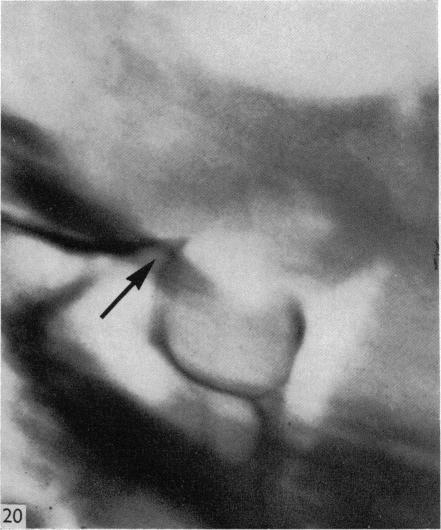

Surgical aspects of the anatomy of the sphenoidal sinuses and the sella turcica.

J Anat. 1977 Dec;124(Pt 3):541-53.